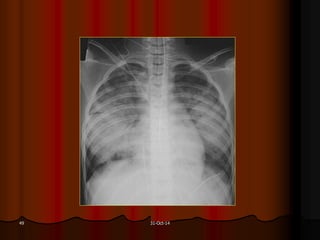

31-Oct-1448

31-Oct-1449